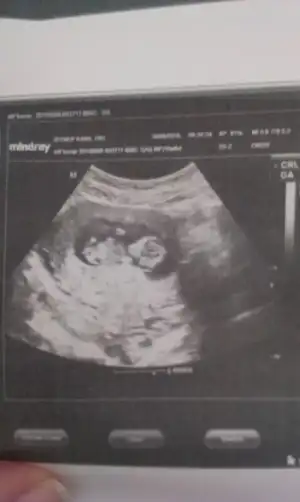

Kızlar ben yeni üyeyim.bir kızım var,ikinciye hamileyim.12+1günlük ultrason görüntüsünü yüklüyorum.bana da yorum yapar mısıniz?dr bacakları kapalı,göremedim.bu halde tahminde bulunursam kız gibi dedi.bu haftalarda yanılma payı çok olur diye yorum yapmak istemedi,ben ısrar edince kız gibi dedi.bacak arası kapalı olunca böyle düşündügünü söyledi.

benim bebişim içinde tahmin de bulunur musunuz?yukarıda ultrason görüntüsünü yükledim.4boyutlu görüntüsünü de yüklüyorum.15.hafta da net bişey söyleriz dedi dr.

Orkidecim,bir yorum da benim bebişime yapabilir misin?burda ki görüntülere bakınca ben kıza benzettim.2hafta sonra dr gidecem.kızlar sizlerden yorum bekliyorum